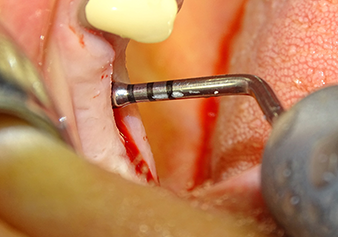

The Schneiderian membrane is carefully detached with the Z25P instrument (phase 1)

Fig.3: Following marking of the implant position and initial expansion of the bed, the Schneiderian membrane is carefully detached with the Z25P instrument (phase 1).